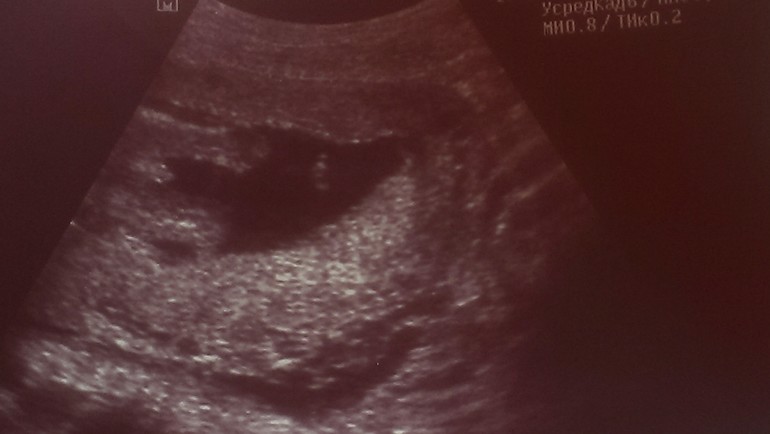

Сын) 18недель.Фото

Ну а это мужское достоинство нашего пацана))